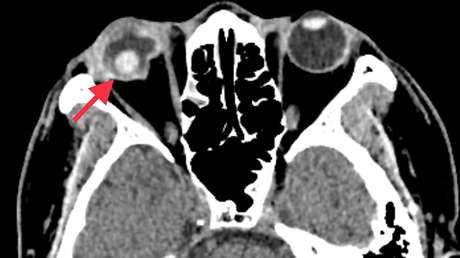

El paciente fue sometido a una cirugía para extraerle una espina de tres milímetros de largo que se le había incrustado. Una tomografía computarizada reveló una ruptura del globo ocular, así como una luxación posterior del cristalino en el interior del ojo.